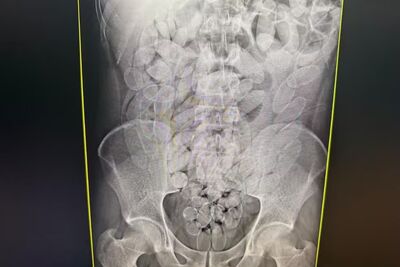

Exame mostra as cápsulas dentro de um dos bolivianos presos. Foto: Divulgação

Os passageiros, sete homens e uma mulher, foram levados à Santa Casa de Corumbá, onde exames de imagem confirmaram que haviam ingerido cápsulas com substância parecida com pasta base de cocaína.